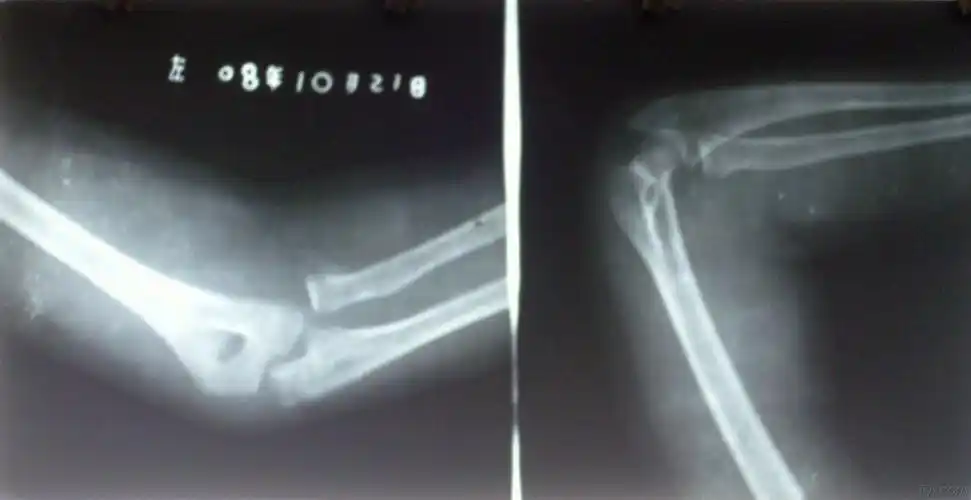

右肱骨内髁骨折并桡骨小头脱位